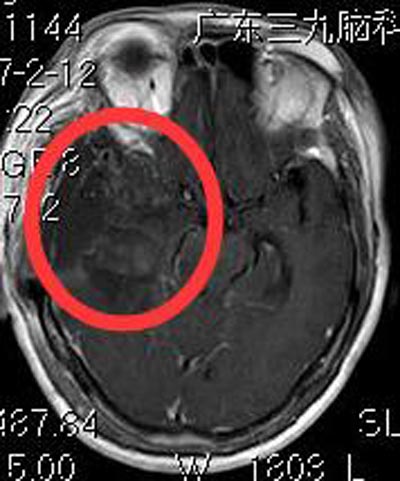

排除手术禁忌症后,综合神经外科鲁明主任主刀在全麻下行右侧小脑幕巨大脑膜瘤切除术,术中显微镜下见灰白色肿瘤组织,质韧,有完整包膜,血供较丰富,术中对颈内动脉、大脑中动脉、大脑前动脉、视神经、动眼神经保护完整,手术顺利。术后,梁女士康复非常顺利。病理结果提示:病变符合(右侧蝶骨嵴)具有神经内分泌分化的肿瘤,由于核仁突出,倾向为非典型脑室外神经细胞瘤,WHO II-III级。

▲术后MR